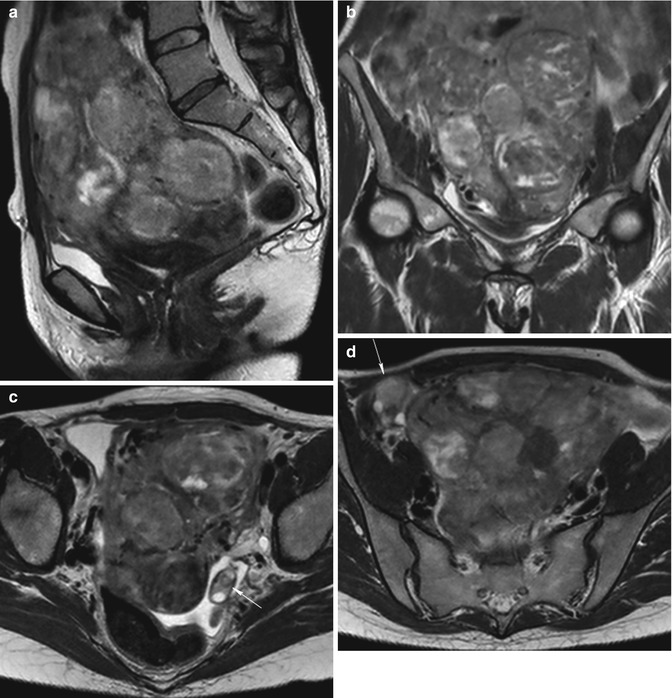

MRI pelvis of a large posterior wall fibroid with cystic degeneration …

Fibroids | Radiology Key

MR imaging of atypical fibroids

Pelvic MRI for Fibroids – Why You Need an MRI to Detect Fibroids

Additional pathologies found during uterine fibroid MRI screening. a …

Fibroids UFE | Body MRI

Uterine Fibroid, Mri Scan Photograph by Du Cane Medical Imaging Ltd